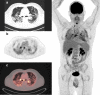

Purpose: [18F]-2-Fluoro-2-deoxy-D-glucose PET/CT (FDG PET/CT) is a sensitive and quantitative technic for detecting inflammatory process. Glucose uptake is correlated with an increased anaerobic glycolysis seen in activated inflammatory cells such as monocytes, lymphocytes, and granulocytes. The aim of the study was to assess the inflammatory status at the presumed peak of the inflammatory phase in non-critically ill patients requiring admission for COVID-19.

Methods: Patients admitted with COVID-19 were prospectively enrolled. FDG PET/CT was performed from day 6 to day 14 of the onset of symptoms. Depending on FDG PET/CT findings, patients' profiles were classified as "inflammatory" or "low inflammatory." FDG PET/CT data were compared with chest CT evolution and short-term clinical outcome. All inflammatory sites were reported to screen potential extra-pulmonary tropism.

Results: Thirteen patients were included. Maximum standardized uptake values ranged from 4.7 to 16.3 in lungs. All patients demonstrated increased mediastinal lymph nodes glucose uptake. Three patients (23%) presented mild nasopharyngeal, two patients (15%) bone marrow, and five patients (38%) splenic mild increase in glucose uptake. No patient had significant digestive focal or segmental glucose uptake. There was no significant physiological myocardial glucose uptake in all patients except one. There was no correlation between PET lung inflammatory status and chest CT evolution or short-term clinical outcome.

Conclusion: Inflammatory process at the presumed peak of the inflammatory phase in COVID-19 patients is obvious in FDG PET/CT scans. Glucose uptake is heterogeneous and typically focused on lungs.